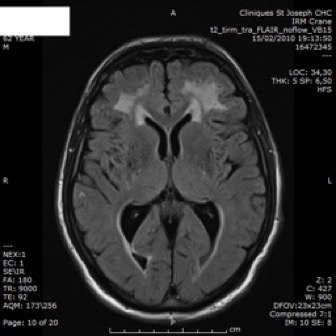

IRM

- anomalies de la substance blanche: LEP

- infarctus de petite taille, souvent profonds: sous-corticaux.